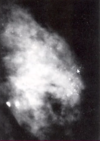

¿Que es el sistema BIRADS?

Es un sistema de reporte estandarizado de lesiones mamarias mediante mastografía

Describe la clasificación BIRADS

BIRADS

- BIRADS 0= Mastografía no útil

- BIRADS 1 = Normal

- BIRADS 2= Mastografía con cambios benignos

- BIRADS 3 = Mastografía con datos probablemente benignos (mayoría de datos benignos, con minoría inconclusos o malignos)

- BIRADS 4 = Sospecha de malignidad

- BIRADS 5 = Alta sospecha de malignidad

Es el método estándar de oro para tamizaje de lesiones malignas de mama

Mastografía

Cuando estan indicados el uso de mastografía + USG de mama como abordaje de estudio de un tumor de la glándula mamaria?

Cuando hay AHF de cáncer de mama en la premenopausia, o tumoración con sospecha clínica de malignidad

Mujer de 32 años que acude a consulta por la aparición de una tumoración en cuadrante superoexterno, de 2.5 cm en tamaño, de superficie irregular, de consistencia dura, fijo a la glándula mamaria, con presencia de edema en tejido mamario adyacente a la tumoración, y LAN supraclaviculares unilaterales,

¿Esta paciente clinicamente que tipo de tumoración tiene?

¿Cual seria el estudio o estudios recomendados?

Tumoración maligna; Mastografía + USG de mama